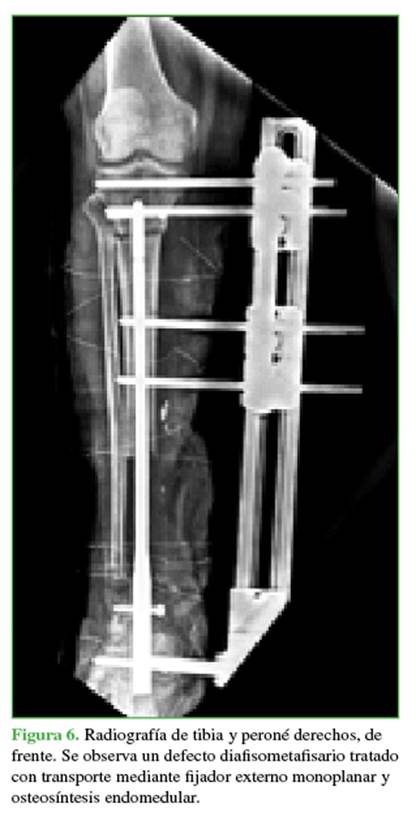

Todos los pacientes siguieron un protocolo de distracción de 1 mm/día dividido en cuatro distracciones de 0,25 mm cada 6 horas (Figura 6).

Tercera etapa